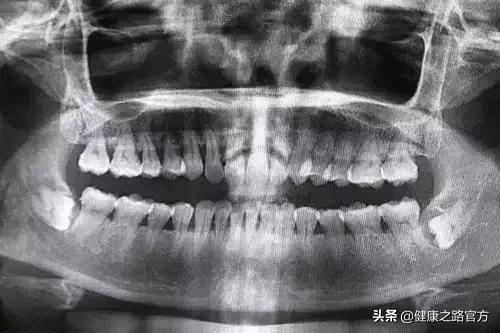

智齒是人的[第三槽牙],是從門牙門縫往兩側數的第8顆牙(上下左右各有一顆)。

所以,若已經開始長智齒了,建議先到正規醫院口腔科拍個牙片,讓醫生根據智齒當前的情況以及預測智齒萌出後可能導致的後果,決定拔還是不拔。

通常,以下情況的智齒都建議拔除:

智齒蛀牙了; 智齒長歪了,甚至橫長、擠到前麵的牙齒,或者與前麵一顆牙形成空隙,導致食物殘渣嵌塞; 得了智齒冠周炎,使智齒牙齦周圍反覆發炎腫痛; 智齒的存在,引發了顳下頜關節綜合徵,或讓你經常咬到臉頰。